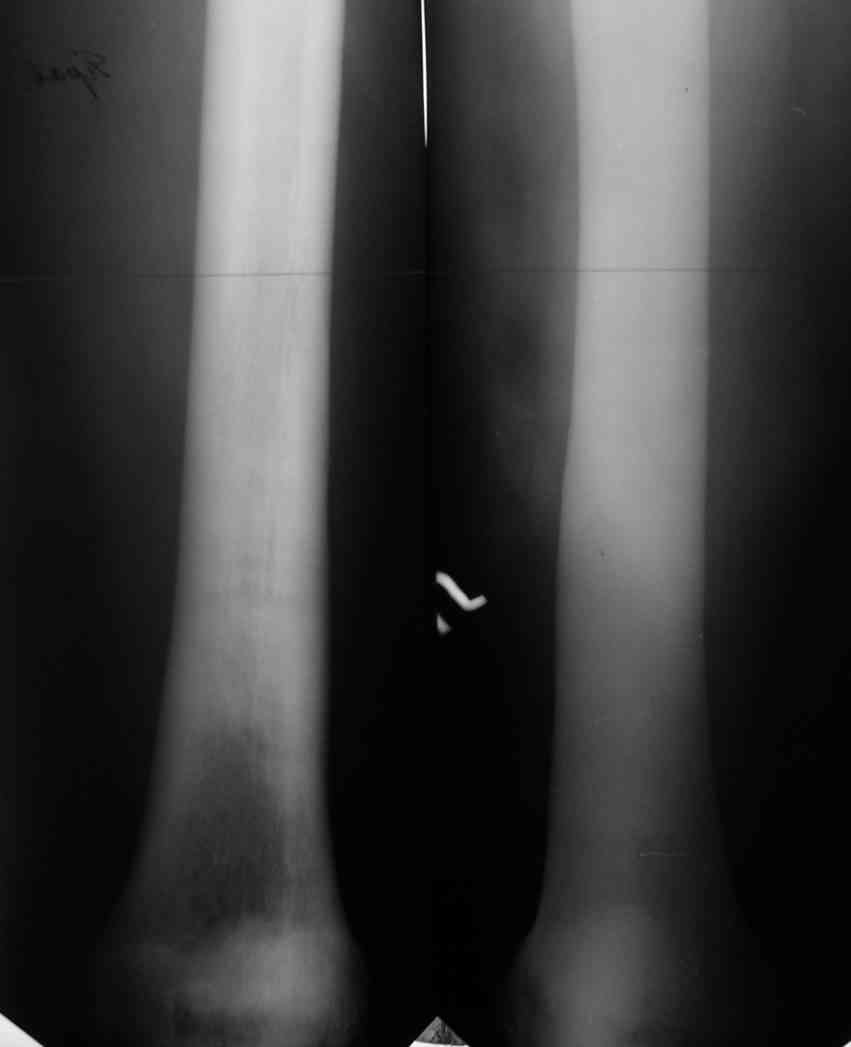

Не являюсь специалистом по костной патологии, но мне кажется, на ренгенограмме множественные мета-диафизарные образования напоминяющее змееподобных извилистых линии и периостеальные ламинирование очень напоминяет картину остеонекроза (инфаркта) костей, возможно связано с длительным применением стероидов.

При предоставлении дополнительных информации, сканнирования, МРТ и лабараторных данных можно уточнить предварительный диагноз, пока склонен к обширному костному инфаркту, и таких больных рекомендуем лечить сиптоматически.

слайды из прошлегодного случая.